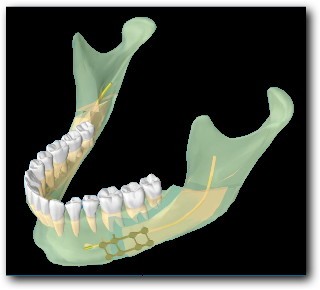

La technique classique est une ostéotomie Basse et longue, le long du nerf alvéolaire inférieur. C’est l’ostéotomie d’Epker, modifiée par Obwegeser. Elle présente pour inconvénient principal d’entrainer une perte de la sensibilité de la lèvre. Par ailleurs, parfois le bord osseux est irrégulier, ce qui peut se voir, ou être inconfortable dans certaines positions.

Les deux premières (Obwegeser et Epker) se ressemblent. La technique d’Eplker est une évolution de la première. Elles présentent toutes les deux l’inconvénient de se réaliser le long du nerf alvéolaire inférieur, et d’entrainer une hypoesthésie partielle dans certains cas (7 à 67% des cas selon les séries).

La technique de l’ostéotomie Haute présente l’avantage de se situer au dessus du nerf. Les pertes de sensibilité sont donc moins fréquentes (0,4 à 0,5% des cas selon les séries).

Ostéotomies Basses

Les ostéotomies basses peuvent être intéressantes dans certaines asymétries horizontales, mais augmentent le risque de troubles de la sensibilité de la lèvre en post-opératoire. Par ailleurs, elles ne permettent pas d’abaisser l’angle de la mandibule dans les asymétries verticales, et une décalage osseux du bord inférieur peut être gênant.

Ostéotomies Hautes

L’ostéotomie Haute de la mandibule est plus courte et diminue donc le risque d’atteinte du nerf alvéolaire inférieur (qui détermine la sensibilité de la lèvre inférieure). Elle permet également de remonter ou d’abaisser l’angle de la mandibule, sans que le décalage osseux ne puisse être visible ou palpable. Il s’agit d’une technique mini-invasive dont les suites sont simples.

Technique Chirurgicale

La technique chirurgicale a été décrite décrite par Perthes Schliessmann en 1932. Il s’agit de l’ostéotomie mandibulaire Haute, ou courte, ou sus-spigienne. La plus grande difficulté est technique, puisque l’ostéosynthèse est très haute. Le tournevis contre-angle de Fritzemeier permet de limiter la taille de l’incision. Cet instrument permet de réaliser une chirurgie mini-invasive.

Avantages de la technique

Il s’agit d’une technique mini-invasive, avec une plus petite incision, et donc des suites moins lourdes (moins de gonflements, moins de troubles sensitifs…).

Par ailleurs, il y a moins de décalage osseux:

- Au niveau du bord inférieur, il n’y a pas de décalage palpable juste sous la peau, contrairement à l’autre technique.

- Les angles mandibulaires peuvent être abaissés, il est donc possible de corriger une asymétrie de hauteur. Ce n’est pas possible avec la technique classique (voir ci-dessous).

- Les angles mandibulaires sont moins déplacés dans la largeur, il y a donc moins d’élargissement des angles, et moins de répercussions sur les ATM.